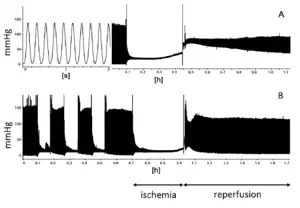

Restoration of blood supply to ischemic tissues can cause additional damage known as reperfusion injury that can be more damaging than the initial ischemia. Reintroduction of blood flow brings oxygen back to the tissues, causing a greater production of free radicals and reactive oxygen species that damage cells. It also brings more calcium ions to the tissues causing further calcium overloading and can result in potentially fatal cardiac arrhythmias and also accelerates cellular self-destruction. The restored blood flow also exaggerates the inflammation response of damaged tissues, causing white blood cells to destroy damaged cells that may otherwise still be viable.[11]